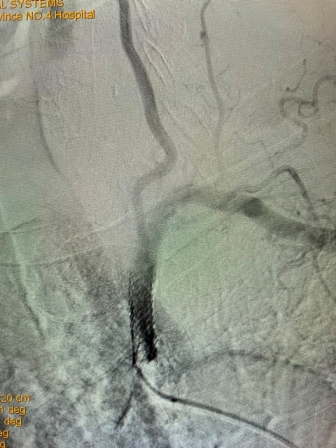

该患者是一位79岁老年男性,门诊以“头晕伴走路不稳”主诉入院。既往有高血压、冠心病PCT术后、慢阻肺病史。入院后完善相关检查,行B超检查考虑“左侧锁骨下动脉盗血”,进一步检查DSA全脑血管造影术时发现:“左侧锁骨下动脉闭塞,左侧锁骨下动脉盗血”。为解决患者疾病痛苦及改善其生活质量,神经内科任主任刘蔚玲主持召集专家团队讨论并精心安排,在客座教授刘亚民周密指导下,由神经内科侯有荣副主任医师、孟军鹏主治医师、赵荣健等骨干医生,通过开通闭塞处血管、球囊扩张后置入支架,手术顺利,术后造影显示患者左侧锁骨下动脉血流再通,锁骨下动脉盗血现象消失,血管再开通,患者术后无明显不适、后循环缺血症状消失。手术极大地改善了其生活质量,同时也有效地预防了严重的脑卒中事件的发生。

(术前造影) (手术后造影)

此例高龄患者、锁骨下动脉闭塞后再通、同时联合椎动脉狭窄病变的同期治疗,其手术复杂、难度大、风险高,神经介入手术创伤小,恢复快,效果立竿见影,其闭塞血管的顺利开通为预防其以后再发生脑梗死奠定了极为重要的基础。该例手术成功完成,再次标志着我院神经内科(卒中中心)神经介入技术水平更上一层新台阶。(采编 党委宣传部)